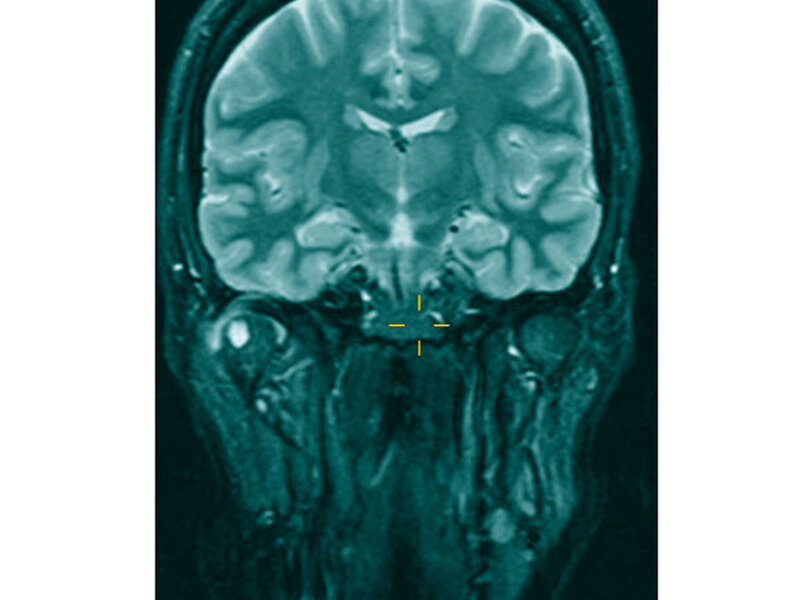

Im Rahmen der klinischen Untersuchung zeigte sich die sonografische Darstellung des Kiefergelenks und dessen angrenzender Strukturen als unzureichend, so dass zur weiteren Diagnostik eine Kontrastmittel-gestützte MRT-Untersuchung des Kiefergelenks eingeleitet wurde (Abbildung 1).

Beim bildmorphologischen Nachweis eines mäßigen Gelenkergusses mit irregulär verdickter, vermehrt Kontrastmittel aufnehmender Synovia, einer ventral gelegenen 2,2 cm x1,3 cm messenden, T2-hyperintensen Läsion mit tubulärer Verbindung zum Gelenkkavum sowie einer 6 mm durchmessenden zystischen Läsion mit randständigem Kontrastmittel-Enhancement im rechten Mandibulaköpfchen ergab sich der differenzialdiagnostische Verdacht auf eine Gicht, eine Pseudogicht oder eine Erkrankung aus dem rheumatoiden Formenkreis.